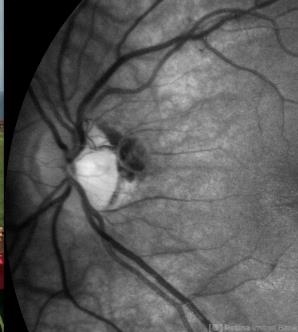

- Unusual presentation of VHL juxtapapillary hemangioblastoma detached from retina with feeder vessels

- Von Hippel-Lindau, retinal hemangioblastoma

- 30-year-old female with fhx VHL and CNS hemangioblastomas and visceral lesions. P/C with a floater (no PVD or VH) after episodes of vomiting.